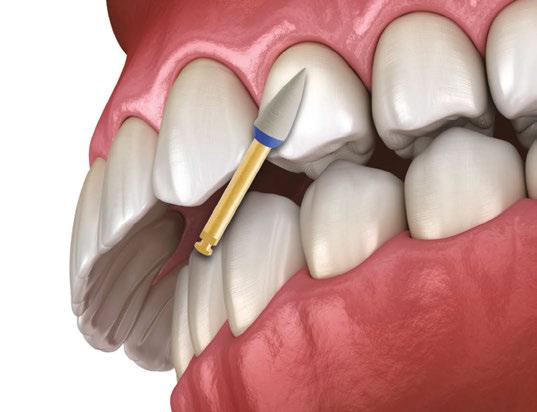

Diamond-coated disks

For cases where there is no overlapping of adjacent teeth, diamond-coated disks (Superflex, SS White, Lakewood, New Jersey) can be effectively used. These disks, available in single and double-sided options (Figure 5), are mounted on a slow-speed straight nose handpiece. To prevent accidental soft tissue injury, the use of a lip retractor is recommended. Due to the potential for soft tissue damage, the use of diamond-coated disks is primarily restricted to the anterior region (maxillary and mandibular).

When using a single-sided disk, the proximal surface of one tooth is modified first (Figure 6B), followed by the adjacent tooth after repositioning the handpiece 180 degrees (Figure 6C). For optimal results, the disk should be aligned parallel to the desired midline or vertical axis.